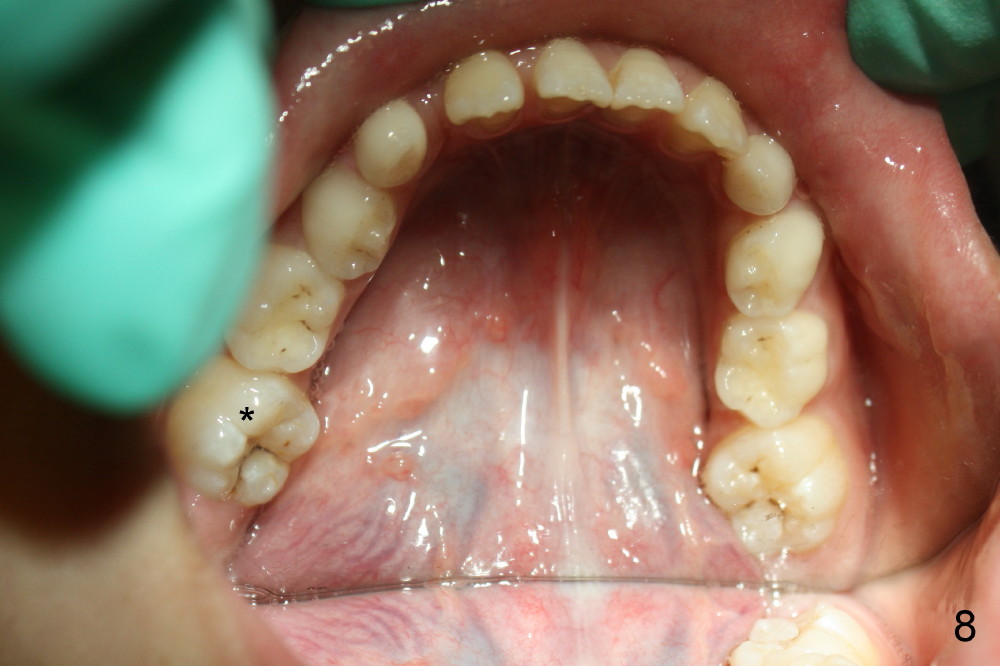

It appears that the chin deviates to the left (Fig.1). The lower dental midline also deviates (Fig.2,4). Profile shows possible bimaxillary protrusion (Fig.3). There is cross bite (deep overjet?) on the right side of the first permanent molars (Fig.5 mirror image), whereas the left posteriors apparently present edge-to-edge occlusion (Fig.6). Fig.7,8 are mirror views of the upper and lower arches, respectively. Panoramic X-ray demonstrates elongation of the right condyle (Fig.9). The right ramus appears to be longer than the left.